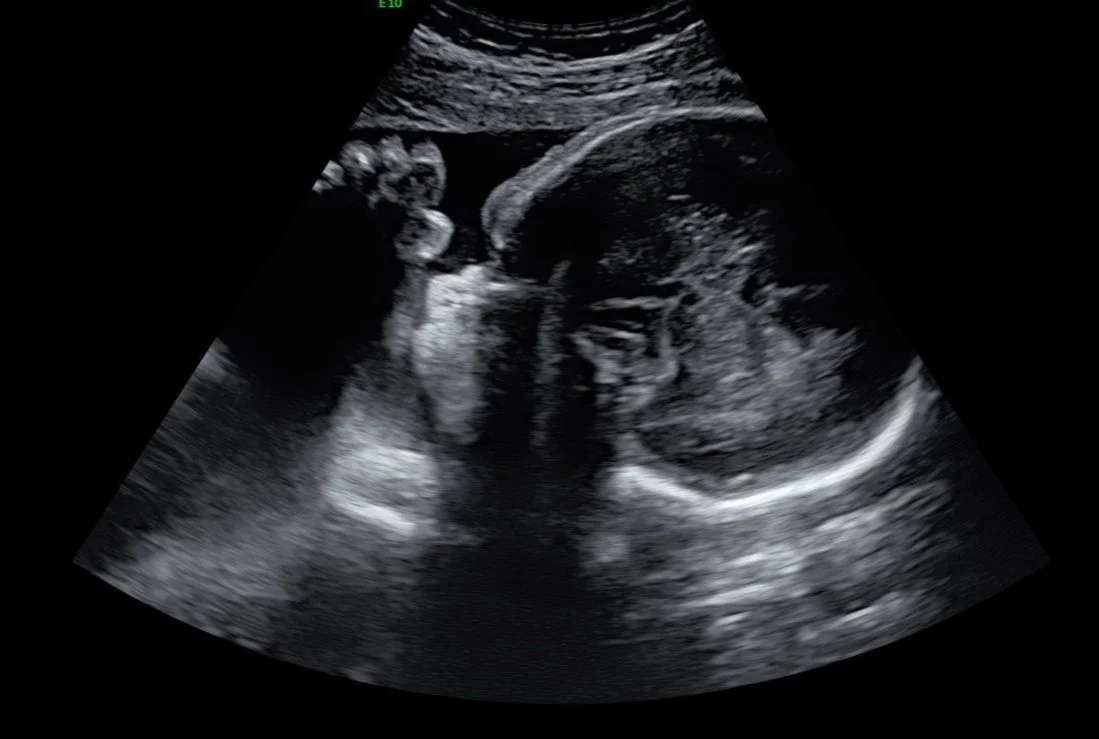

Seeing your baby suck their thumb, purse their little lips together, rub their eyes, and kick their little feet is magical.

Ultrasound image of a fetus inside the womb.

During your session, you’ll watch your baby in real time—seeing their movements, their expressions, their unique rhythms. These are moments of life in utero that are usually unseen, yet deeply felt. Many families describe it as the first time everything becomes real in a new way.